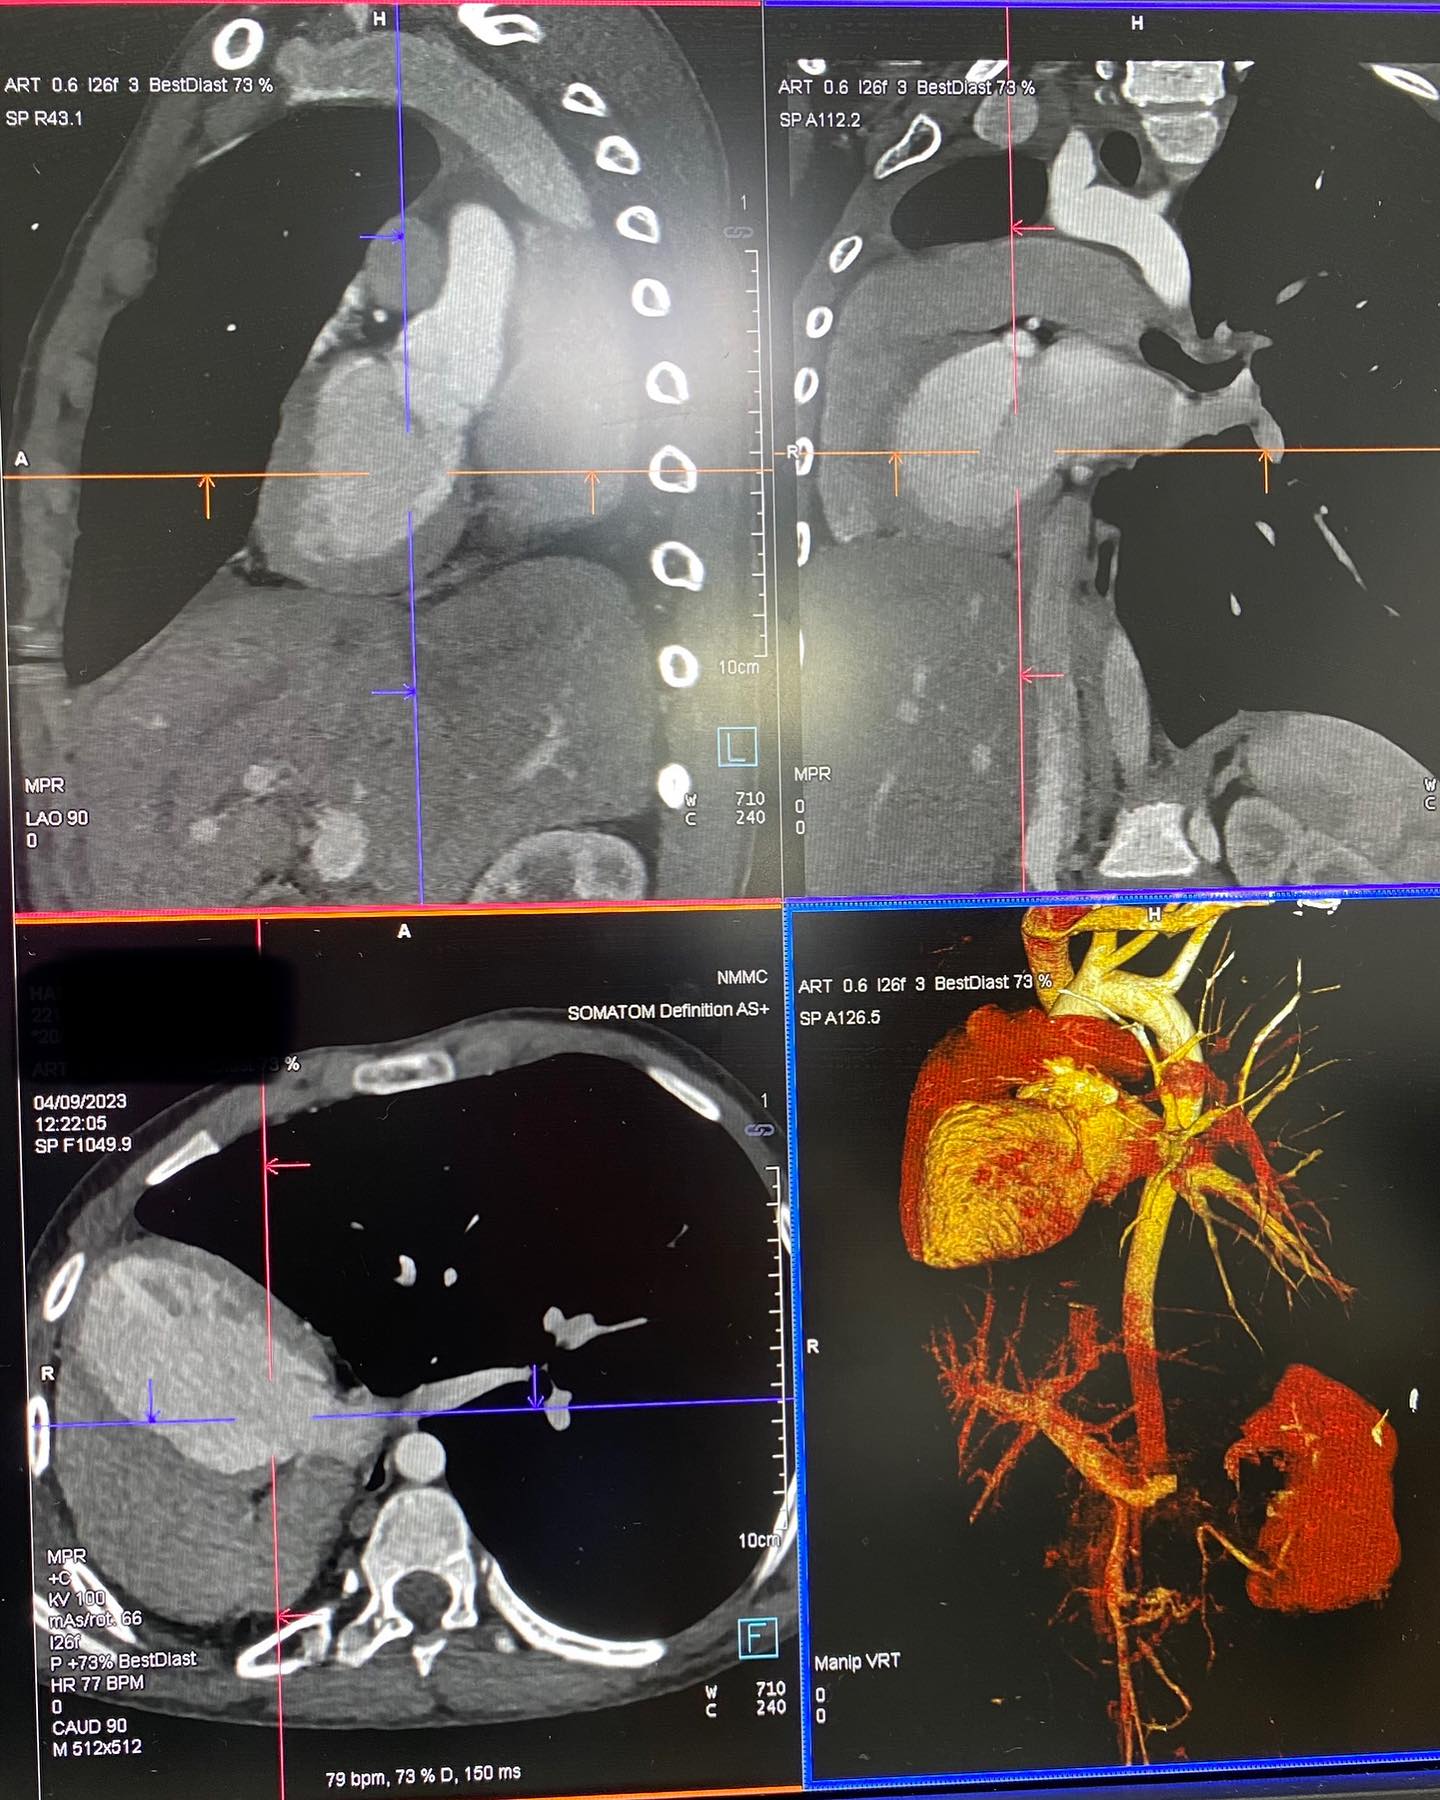

Էխոսրտագրության ժամանակ երեխայի սիրտը աջից էր, սակայն դա սովորական դեկստրակարդիա չէր, ինչը բժշկի մոտ կասկած առաջացրեց, որի կապակցությամբ կատարվեց կրծքավանդակի կոնտրաստ համակարգչային տոմոգրաֆիա։

Արդյունքը տպավորիչ էր։ Երեխայի մոտ առկա էր աջ թոքի ագենեզիա (թոքը չի զարգացել, համապատասխանաբար բացակայում էին նաև աջ գլխավոր բրոնխը, աջ թոքային զարկերակը և աջ թոքային երակները), ինչի հետևանքով միջնորմը (այդ թվում սիրտը) տեղակայված է կրծքավանդակի աջ կեսում։

Սրտի նման տեղակայումը հեմոդինամիկ շեղումներ չի առաջացրել. երեխան ունի կառուցվածքային առողջ սիրտ։